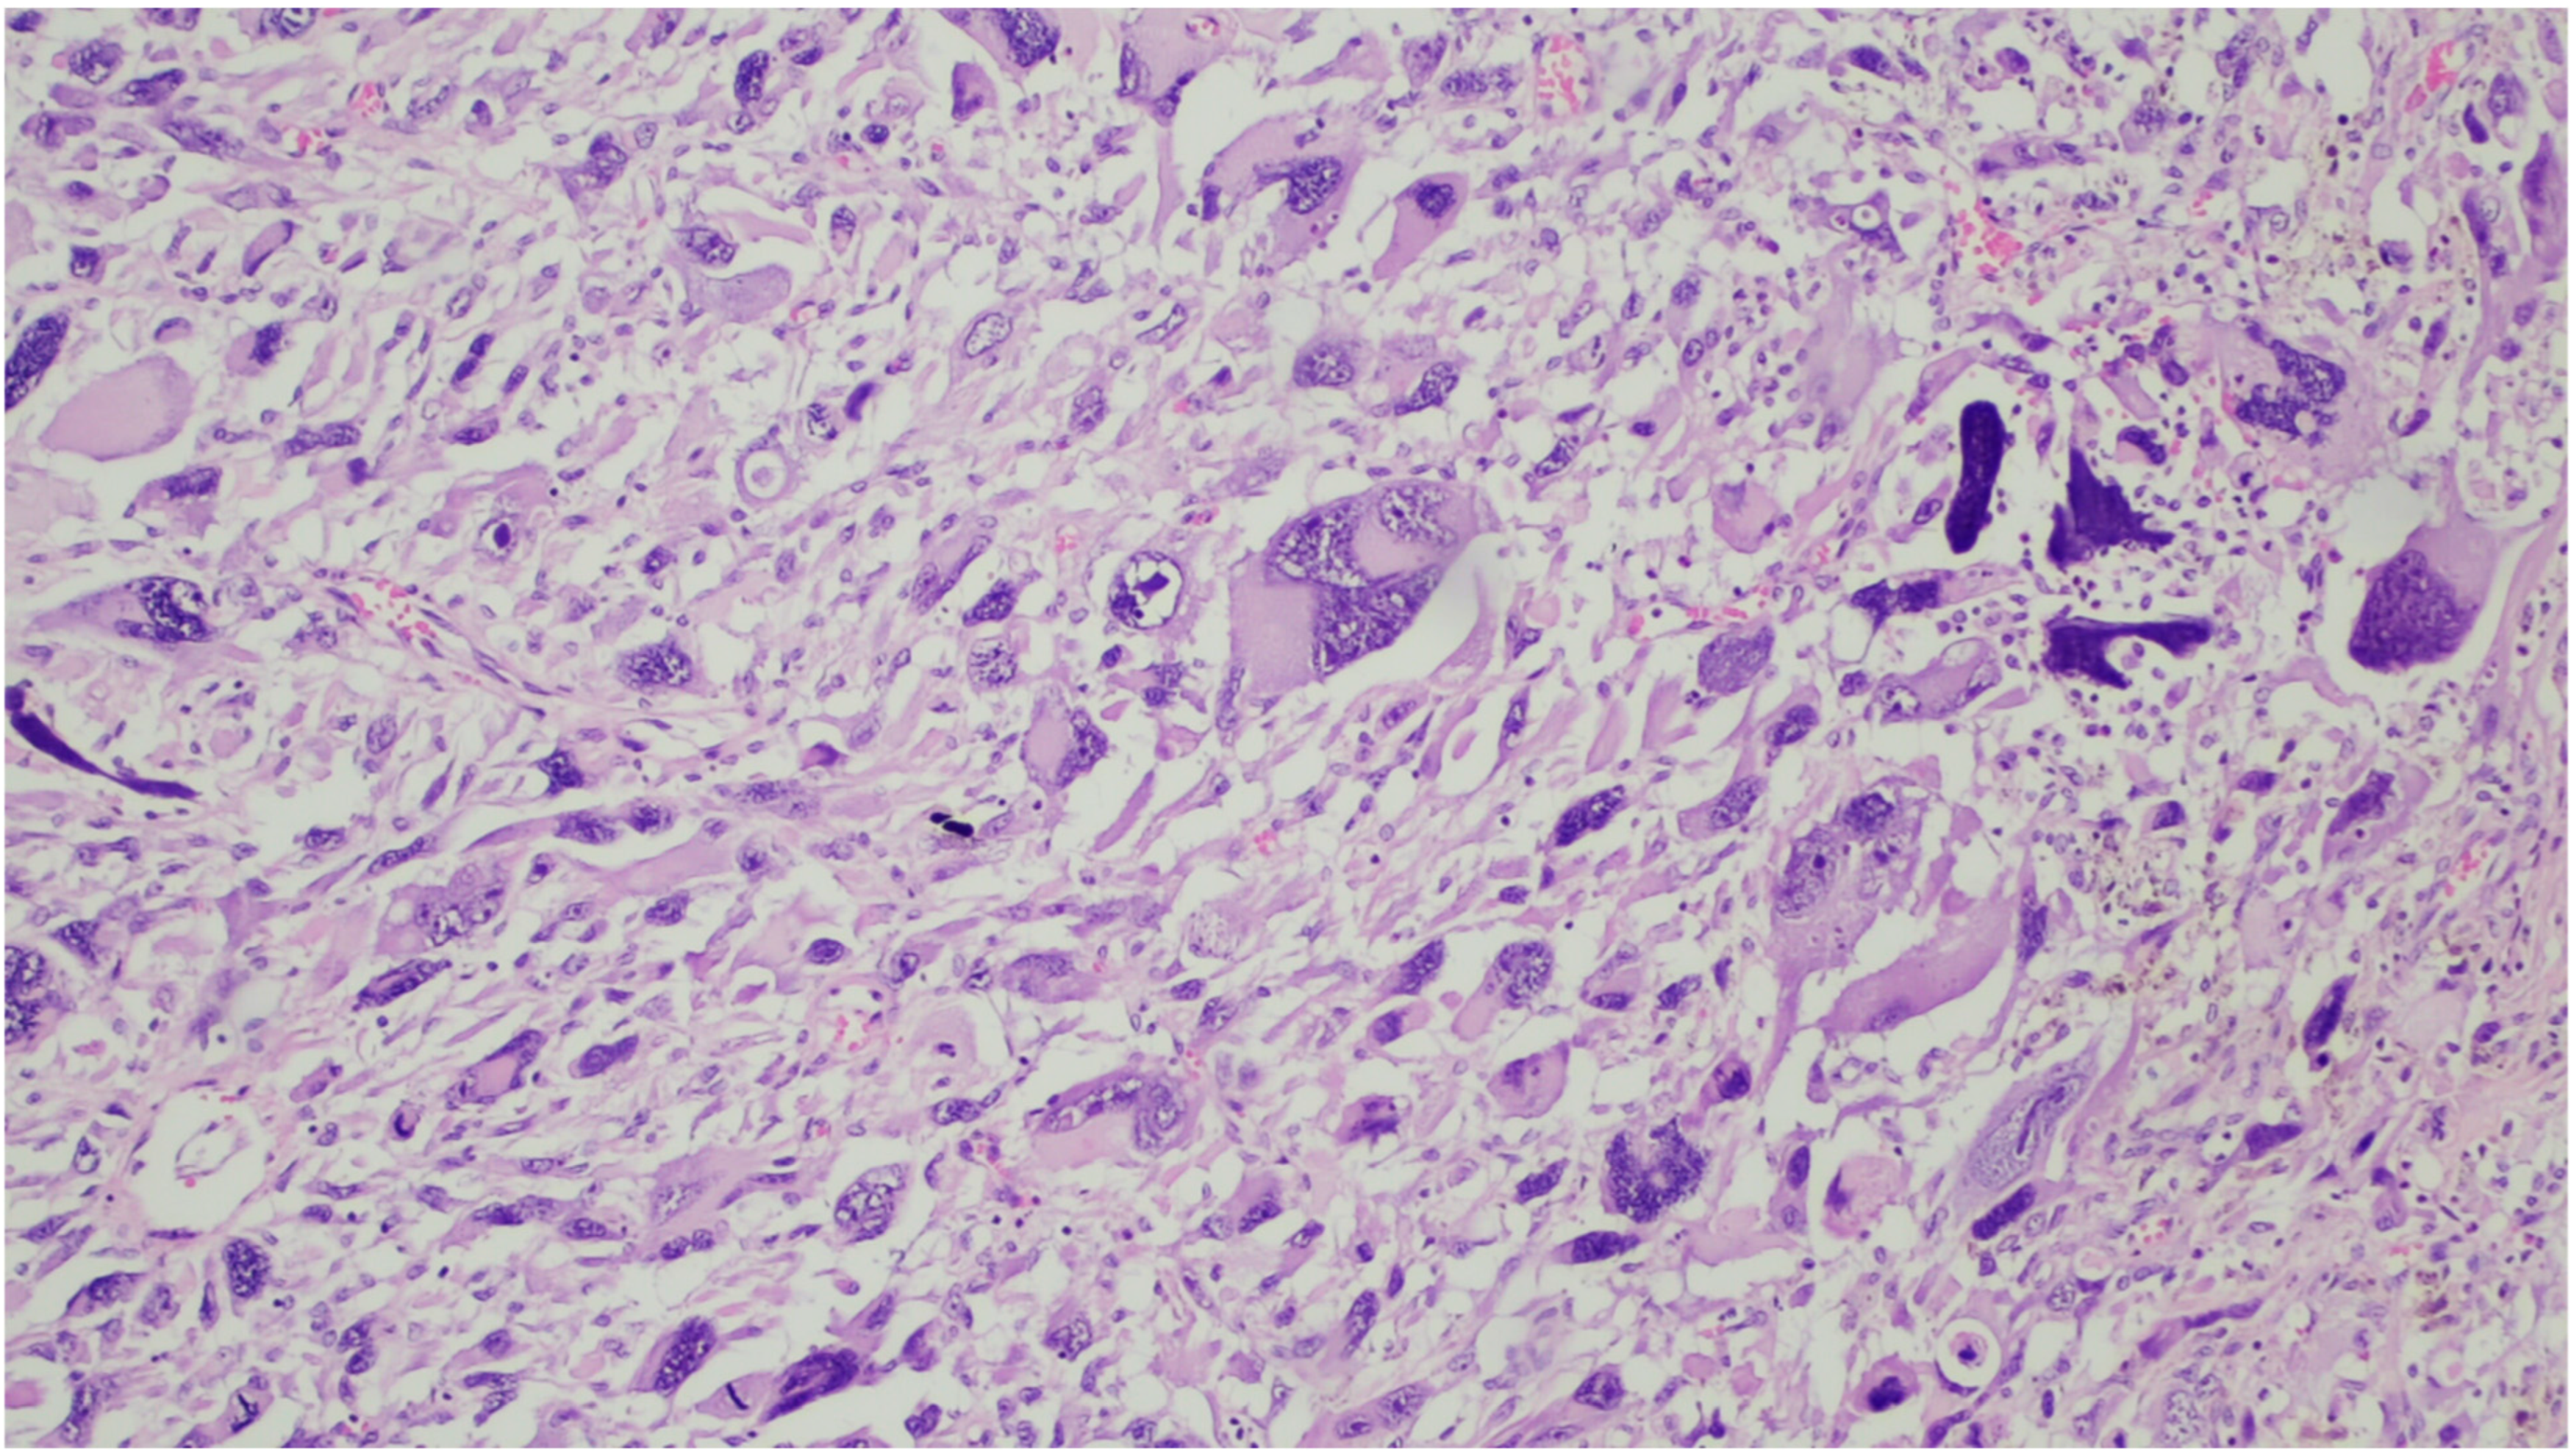

6. Gross and Histologic Features